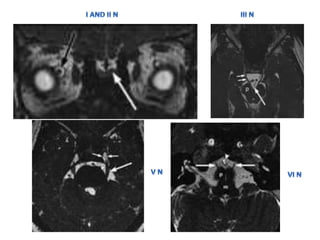

• CISS / 3D FIESTA(fast imaging employing steady-

state acquisition) SEQUENCE

• Heavily T2 Wtd Sequences

• Allows much higher resolution and clearer

imaging of tiny intracranial structures

CRANIAL NERVES IMAGING

• CISS /3D FIESTA(fast imaging employing steady- state acquisition) SEQUENCE • Heavily T2 Wtd Sequences • Allows much higher resolution and clearer imaging of tiny intracranial structures CRANIAL NERVES IMAGING